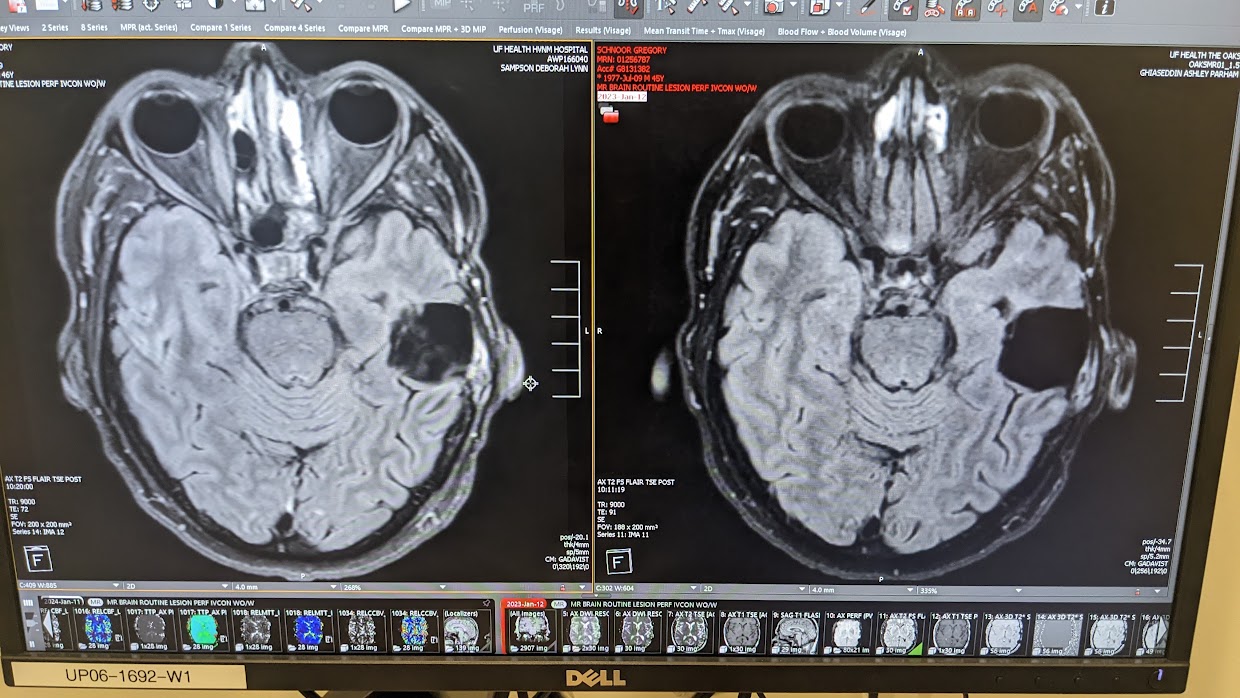

Diagnosed.

Not Defeated.

Fifteen years ago I was handed a diagnosis that would stop most people in their tracks — malignant brain cancer. I had brain surgery, chemotherapy, and radiation. I had never run a day in my life.